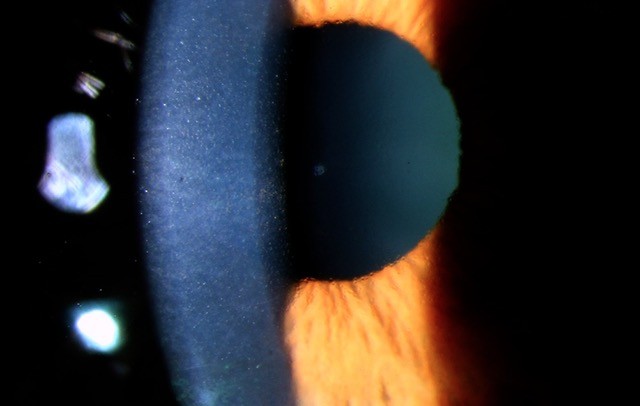

Tattoo-associated uveitis risk flagged

Staff reporters 09/02/2026

Tattoo-associated uveitis becoming a regular occurrence in Australia